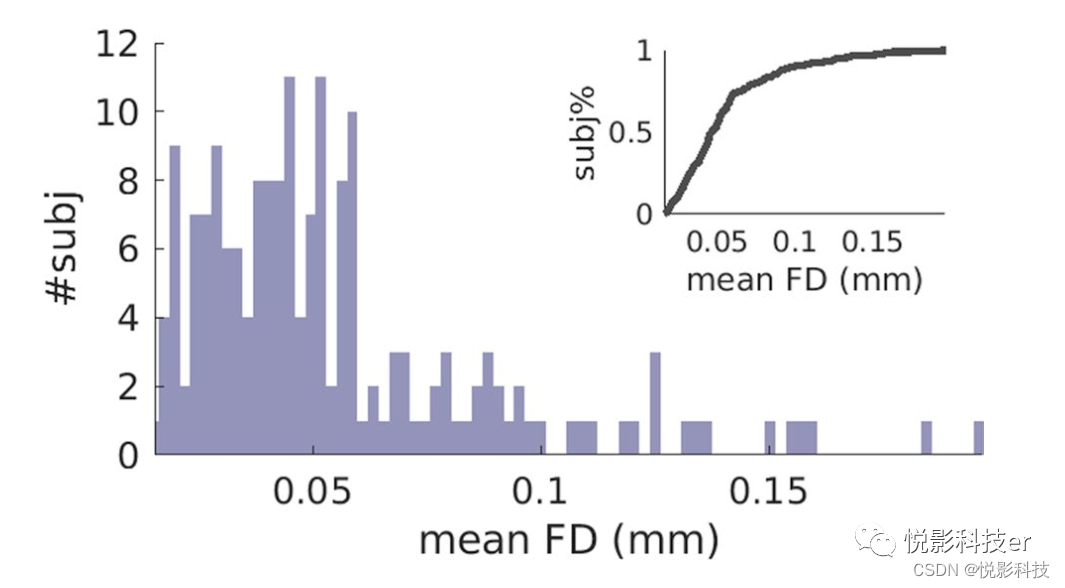

t1加权图像校正强度不均匀性,然后使用FreeSurfer(版本5.3.0)进行颅骨剥离。一名训练有素的研究人员根据https://surfer.nmr.mgh.harvard.edu/fswiki/FsTutorial/TroubleshootingData上给出的指示进行了后期处理质量检查。对rs-fMRI数据进行切片定时、运动校正、颅骨剥离、带通滤波(0.01-0.08Hz)和数据大平均标度(全脑模态值为100)预处理。计算帧内位移(头部运动特征),将rs-fMRI数据显示帧内位移(FD)大于0.5mm的受试者排除在本研究之外。图2显示了受试者间rs-fMRI数据的平均帧内位移分布。本研究中所有受试者的平均FD均小于0.2 mm。其中90%平均FD小于0.1mm。因此,本研究利用6个参数从rs-fMRI信号中回归出头部运动,并从rs-fMRI信号中回归出脑脊液和白质信号。时间带通滤波(0.01-0.08Hz)。对DWI图,在FSL中,利用互信息对图像进行无扩散加权的平滑变换,首先对每个被测对象的图像进行运动和涡流畸变校正。在研究对象中,我们遵循Huang等人中详细介绍的程序来纠正由于大脑中b0易感性差异而导致的DWIs几何失真。简单地说,t2加权图像作为解剖学参考。将无扩散加权的基线图像与t2加权图像相结合的形变表征了DWI的几何畸变。为此,首先使用flirt进行受试者内部配准,以去除扩散加权图像和t2加权图像之间的线性变换(旋转和平移)。大变形异构度量映射(LDDMM)寻求最优非线性变换,使基线图像变形,而不扩散加权到t2加权图像。然后对每幅扩散加权图像进行对称变换,以纠正非线性几何畸变。使用Dhollander等人提出的方法对扩散梯度进行重新定向。最后,我们利用Aganj等提出的基于HARDI的考虑立体角约束的方法估计方向分布函数(odf)。ODF是表征白质纤维取向的水分子扩散概率密度函数的角轮廓。

图2 平均帧位移分布